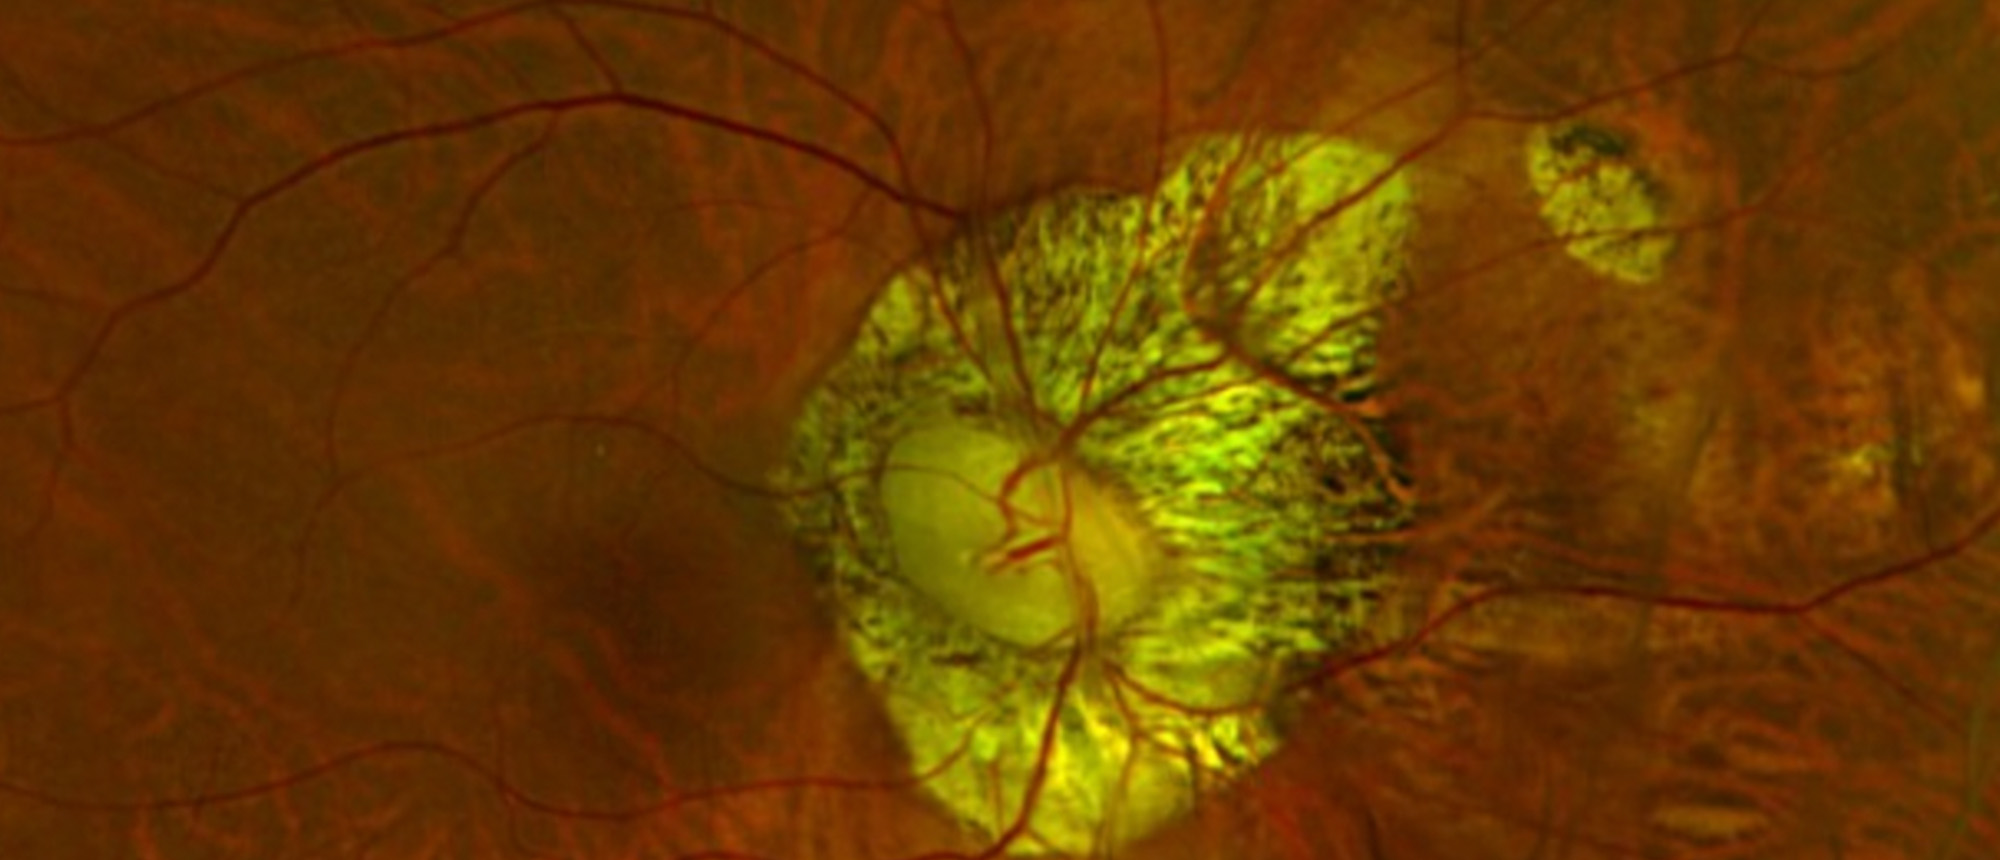

Acute syphilitic posterior placoid chorioretinopathy (ASPPC) is a unique ocular sign of syphilis. It appears as a large, flat, yellowish lesion on the retinal pigment epithelium, typically in the macula. While not seen in every syphilis case, its presence strongly suggests ocular involvement and wa…